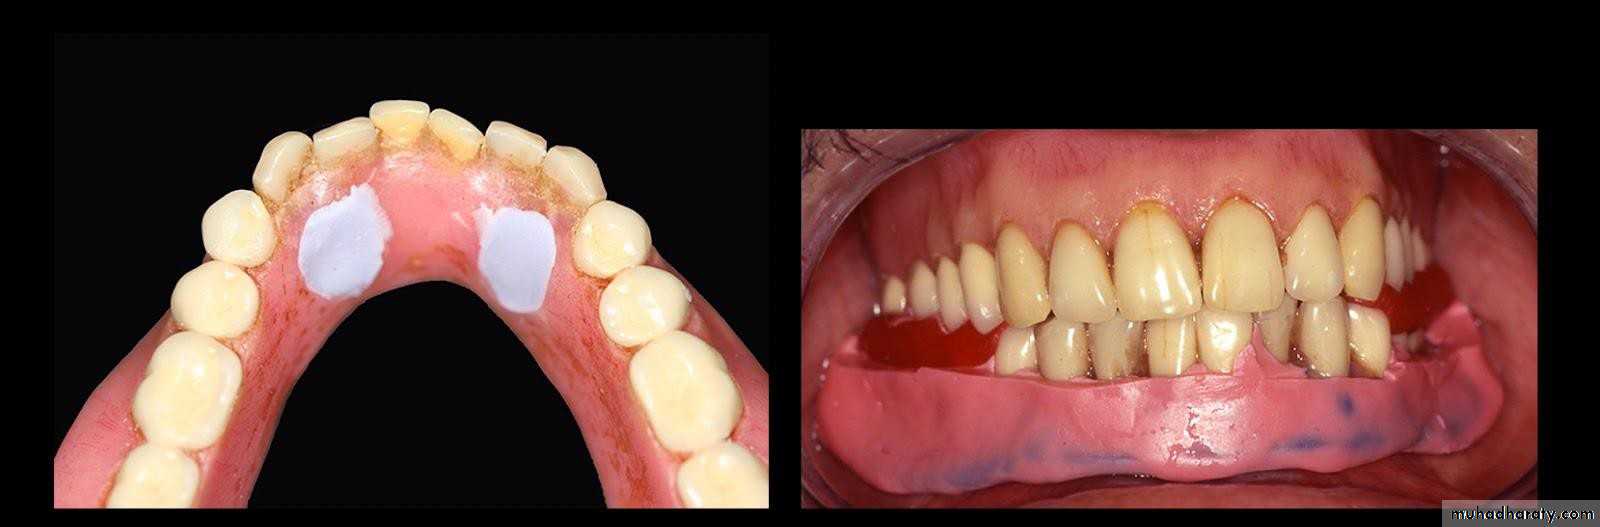

• 1- Simple tooth modification of vital abutment.

• A- Thimble-shaped

• coping• 2- Tooth reduction and cast coping of vital abutment

• B- Tooth reduction• and cast coping

• 2- Tooth reduction and cast coping of vital abutment